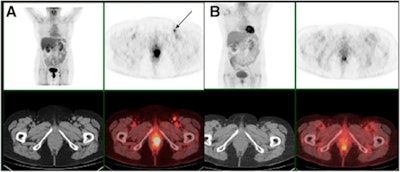

Based on the FDG-PET/CT results, 55 patients (63%) experienced a complete metabolic response to treatment, which was defined as having no abnormal FDG uptake. Thirty-two patients (27%) had abnormal FDG uptake and were considered to have an incomplete response to treatment. Among the latter set of patients, 17 (53%) showed disease progression, while 15 (47%) had a partial metabolic response.

The two-year progression-free survival rate was 96% for patients with a complete metabolic response, compared with 28% for patients with a poor metabolic response to treatment (p < 0.0001). The researchers also evaluated cause-specific survival (CSS), which was defined as the period from treatment initiation to the date of death due to anal cancer. The two-year CSS rate was 100% for patients with a complete metabolic response and only 59% for patients without a complete metabolic response (p < 0.0001).

FDG-PET/CT changed treatment management in 14 cases (16%), which included eight cases of previously unseen local recurrences. The results were confirmed by biopsy and led to salvage surgery for the patients. In addition, one patient avoided an unnecessary biopsy, despite an inconclusive clinical examination and a positive MRI.